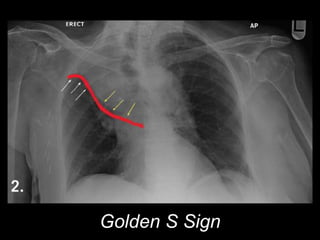

Squamous cell ca

Central Location (2/3)

Atelectasis

"Reverse S sign of Golden”

Post-obstructive pneumonia

May cavitate

Most closely associated with smoking

Golden S Sign